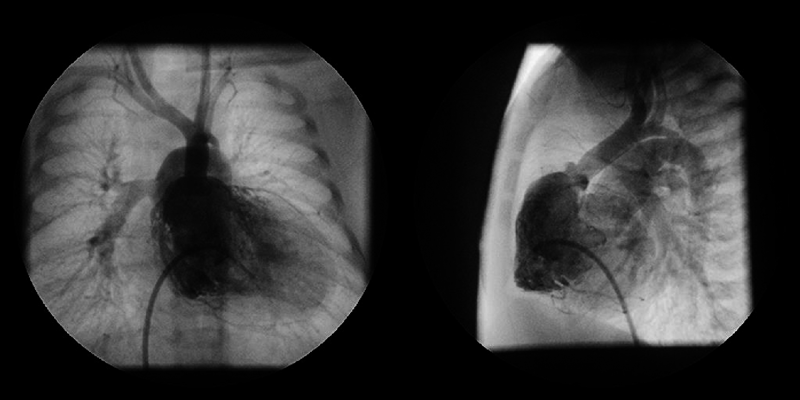

Two years after the operation, the diameter of the TV annulus was found to be 10.8 mm (Z-score: −2.73), and bidirectional flow through ASD was observed on echocardiography. Computed tomography showed that the systemic-to-pulmonary shunt had been occluded, suggesting increased antegrade pulmonary blood flow from the RV. Cardiac catheterization showed a mean PA pressure of 13 mmHg. At the age of 3 years and 6 months, 1.5VR was performed, consisting of the bidirectional Glenn anastomosis, ASD closure, and division of the systemic-to-pulmonary shunt already occluded. The diameter of the TV annulus was measured intraoperatively as 13 mm (Z-score: −2.03). Cardiopulmonary bypass time and cross-clamp time were 174 min and 22 min, respectively. Angiography at 1 year postoperatively showed adequate development of the PAs and unobstructed left ventricular outflow tract (Fig. 2). The SVC and right atrial pressures were 13 mmHg and 6 mmHg, respectively. Thirteen years after the operation, the patient is in a good general condition with normal sinus rhythm. The latest investigation on echocardiography illustrated no sign of right heart failure, such as dilatation of the inferior vena cava, a reversal flow in the inferior vena cava, and right ventricular systolic dysfunction. The TV diameter was 25.3 mm with balanced left and right ventricular cavities (Fig. 3). Table 1 summarizes consecutive changes in the TV diameter, a TV-to-mitral valve diameter ratio, mean PA pressure, and RV end-diastolic pressure. During the course, the patient did not show significant RV diastolic or systolic dysfunction. The TV diameter and RV function did not correlate to each other.

Fig. 2 Left and right ventriculography 1 year after the one and a half ventricular repair

The left ventricular outflow tract has no significant stenosis. The pulmonary arteries are well developed. White arrow indicates the bidirectional Glenn anastomosis.